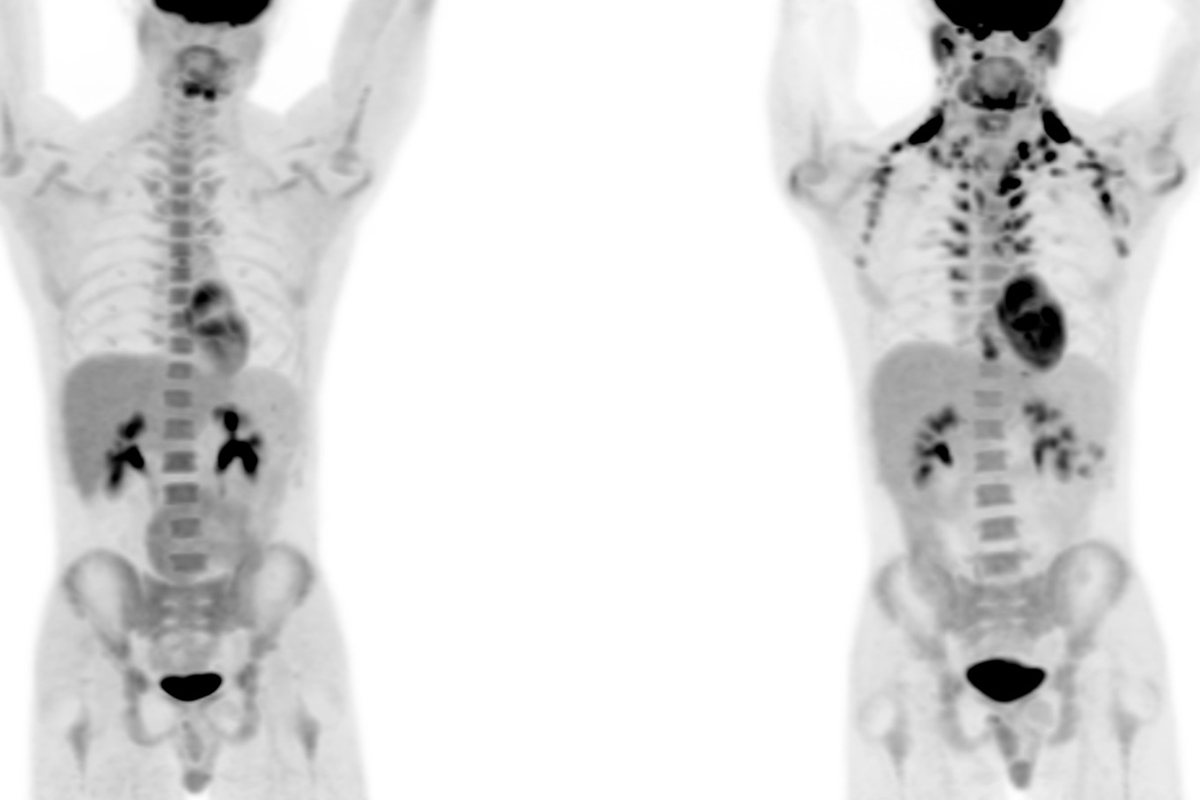

These two PET scans show the absence of brown fat in the shoulder area on the left and the presence of brown fat on the right.

“What people saw in those scans is that the glucose went into the lower neck and shoulder area,” Dr. Wibmer says. “And that was a little scary because that’s actually where a lot of cancers form — lymphoma, for example. A few people in the nuclear medicine world hypothesized early on that it might be brown fat, and everybody said, ‘Are you kidding? Those are adults. Adults do not have brown fat.’ ”